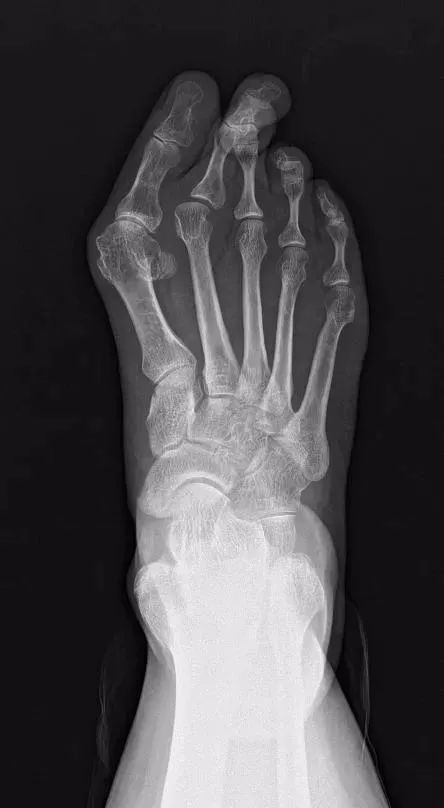

50 多岁的王阿姨,双足后天性踇外翻数年,以右足为甚,由于一直没有正规治疗,畸形日渐严重,近一年来走路时右足底异常疼痛,正常穿鞋也成了困扰。今年 10 月份,王阿姨为了缓解症状,矫正畸形,来到同济医院足踝外科就诊。X 线和 CT 检查显示籽骨已经严重脱位,脚底失去了籽骨的支持,第一跖骨头直接撑地,此外,第二足趾骑跨在第三足趾上,这些症状让王阿姨走路、穿鞋都很困难。

常规的手术方法都是从二维平面上来纠正踇外翻,但事实上踇外翻是一种三维的畸形,常规的术式无法将第一跖骨解剖复位。为了矫正王阿姨的畸形,让王阿姨能够正常的穿鞋和走路,经过仔细的术前准备,杨云峰主任选择了右足第一跖骨截骨+去旋转复位,从三维上将第一跖骨及籽骨恢复到正常解剖位置,第二跖骨采用切开复位+跖板修复手术,将第二足趾完全复位至正常位置,帮助患者解决了穿鞋难、走路痛的问题。

踇外翻畸形是一种常见的足畸形,是指第一跖骨内翻内旋以及趾骨外翻,可合并其它足趾的偏斜、骑跨。除了穿鞋不当以外,肥胖、遗传、年龄、类风湿性关节炎、韧带松弛等原因都可能引起踇外翻畸形的发生。踇外翻是一种复杂的解剖畸形,严重的踇外翻畸形可出现足底的疼痛及感觉减退,此时及早手术才是矫正踇外翻畸形的最佳解决办法。